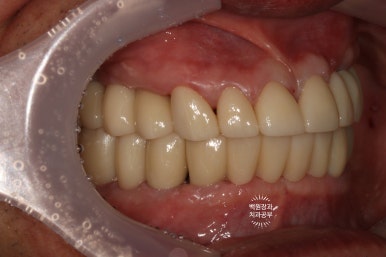

최종보철물 완성 후 측면사진입니다.

임플란트가 저렇게 지그재그로 완벽하게 물리기 쉽지 않습니다.....

환자분의 인내심과 의료진의 노력으로 만들어낸 결과입니다.